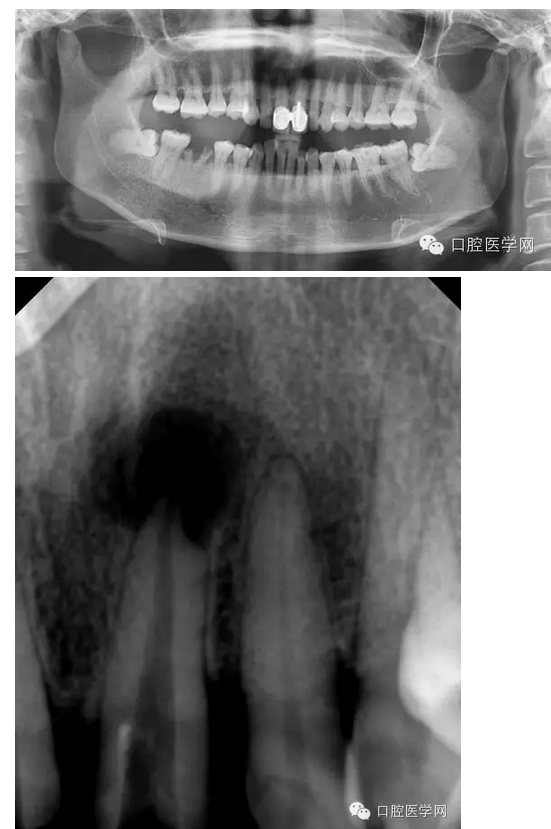

左上1根尖膿腫患者

檢查:21相對(duì)應(yīng)的前庭溝隆起,粘膜紅腫,有波動(dòng)感,門(mén)診(+),叩(++)。

輔助檢查:21x線示根周有大面積陰影

診斷:21急性根尖周炎

治療方案:建議拆除牙冠,21行根管治療,樁核、全冠修復(fù)